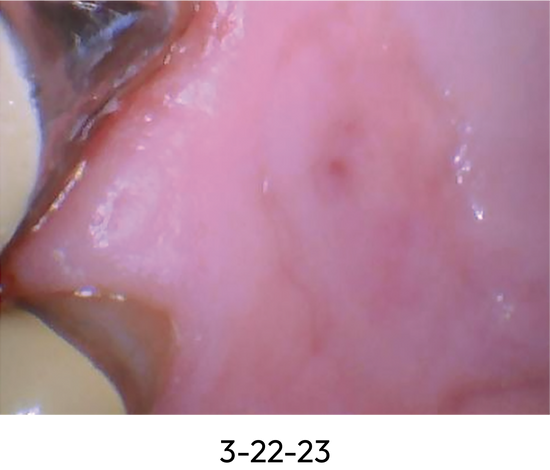

Healing Progression of Oral Lesion with Benova® Mouth Rinse System

Patient PB with diabetes, age 70.

- Patient had painful lesion for several months with no healing.

- Reported pain resolved almost immediately upon using Benova® Mouth Rinse System.